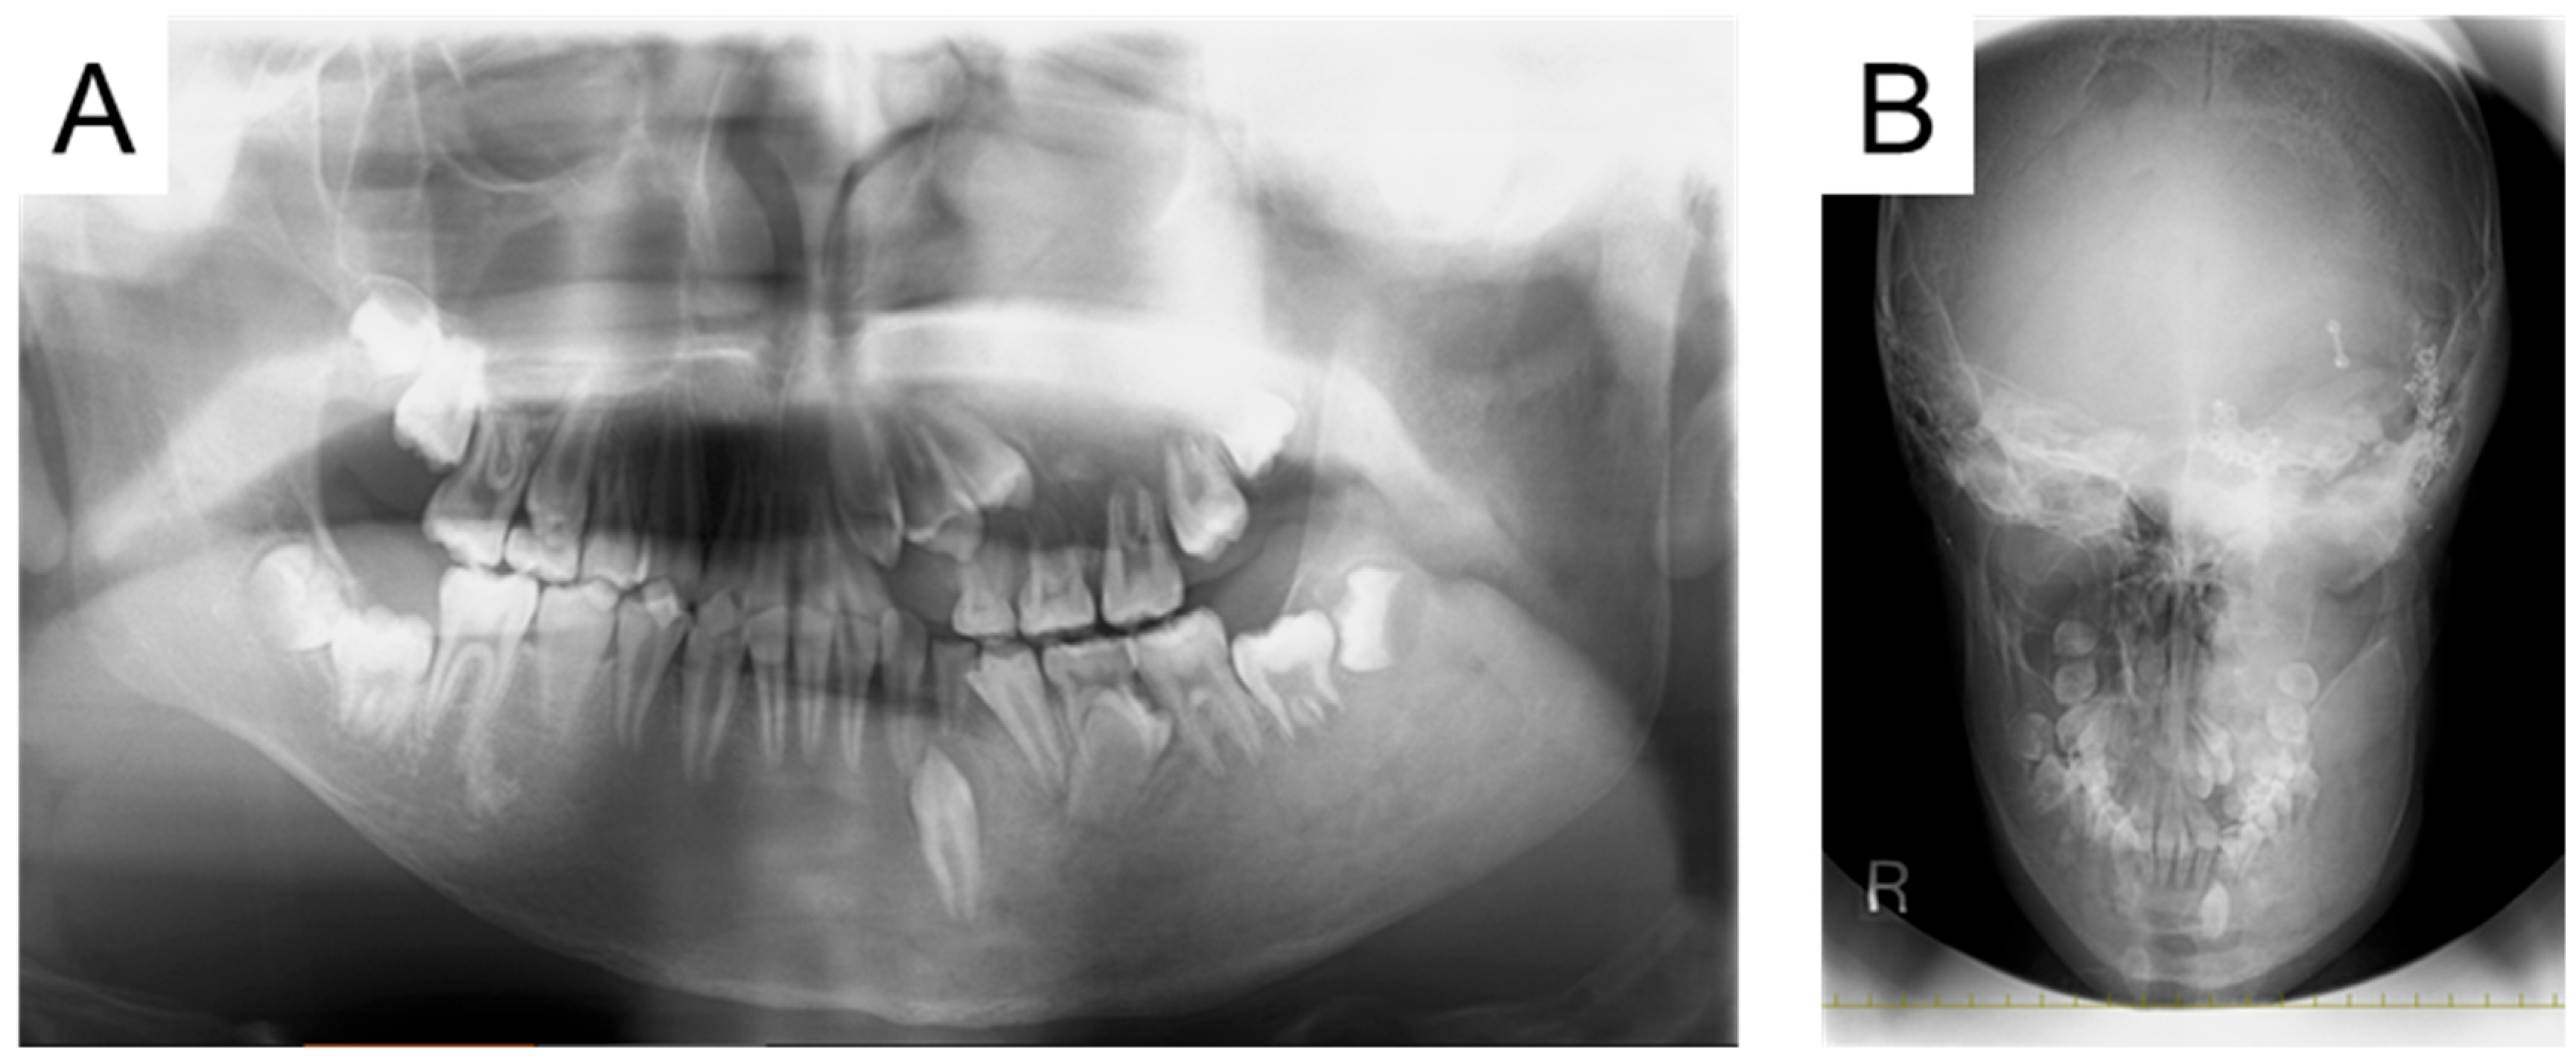

| 5 y | Swelling in the left cheek region |

| 9 y | Diagnosis of MAS and precocious puberty, and start of bisphosphonate therapy |

| 11 y | Optic canal decompression surgery |

| 13 y 7 m | First visit to our department |